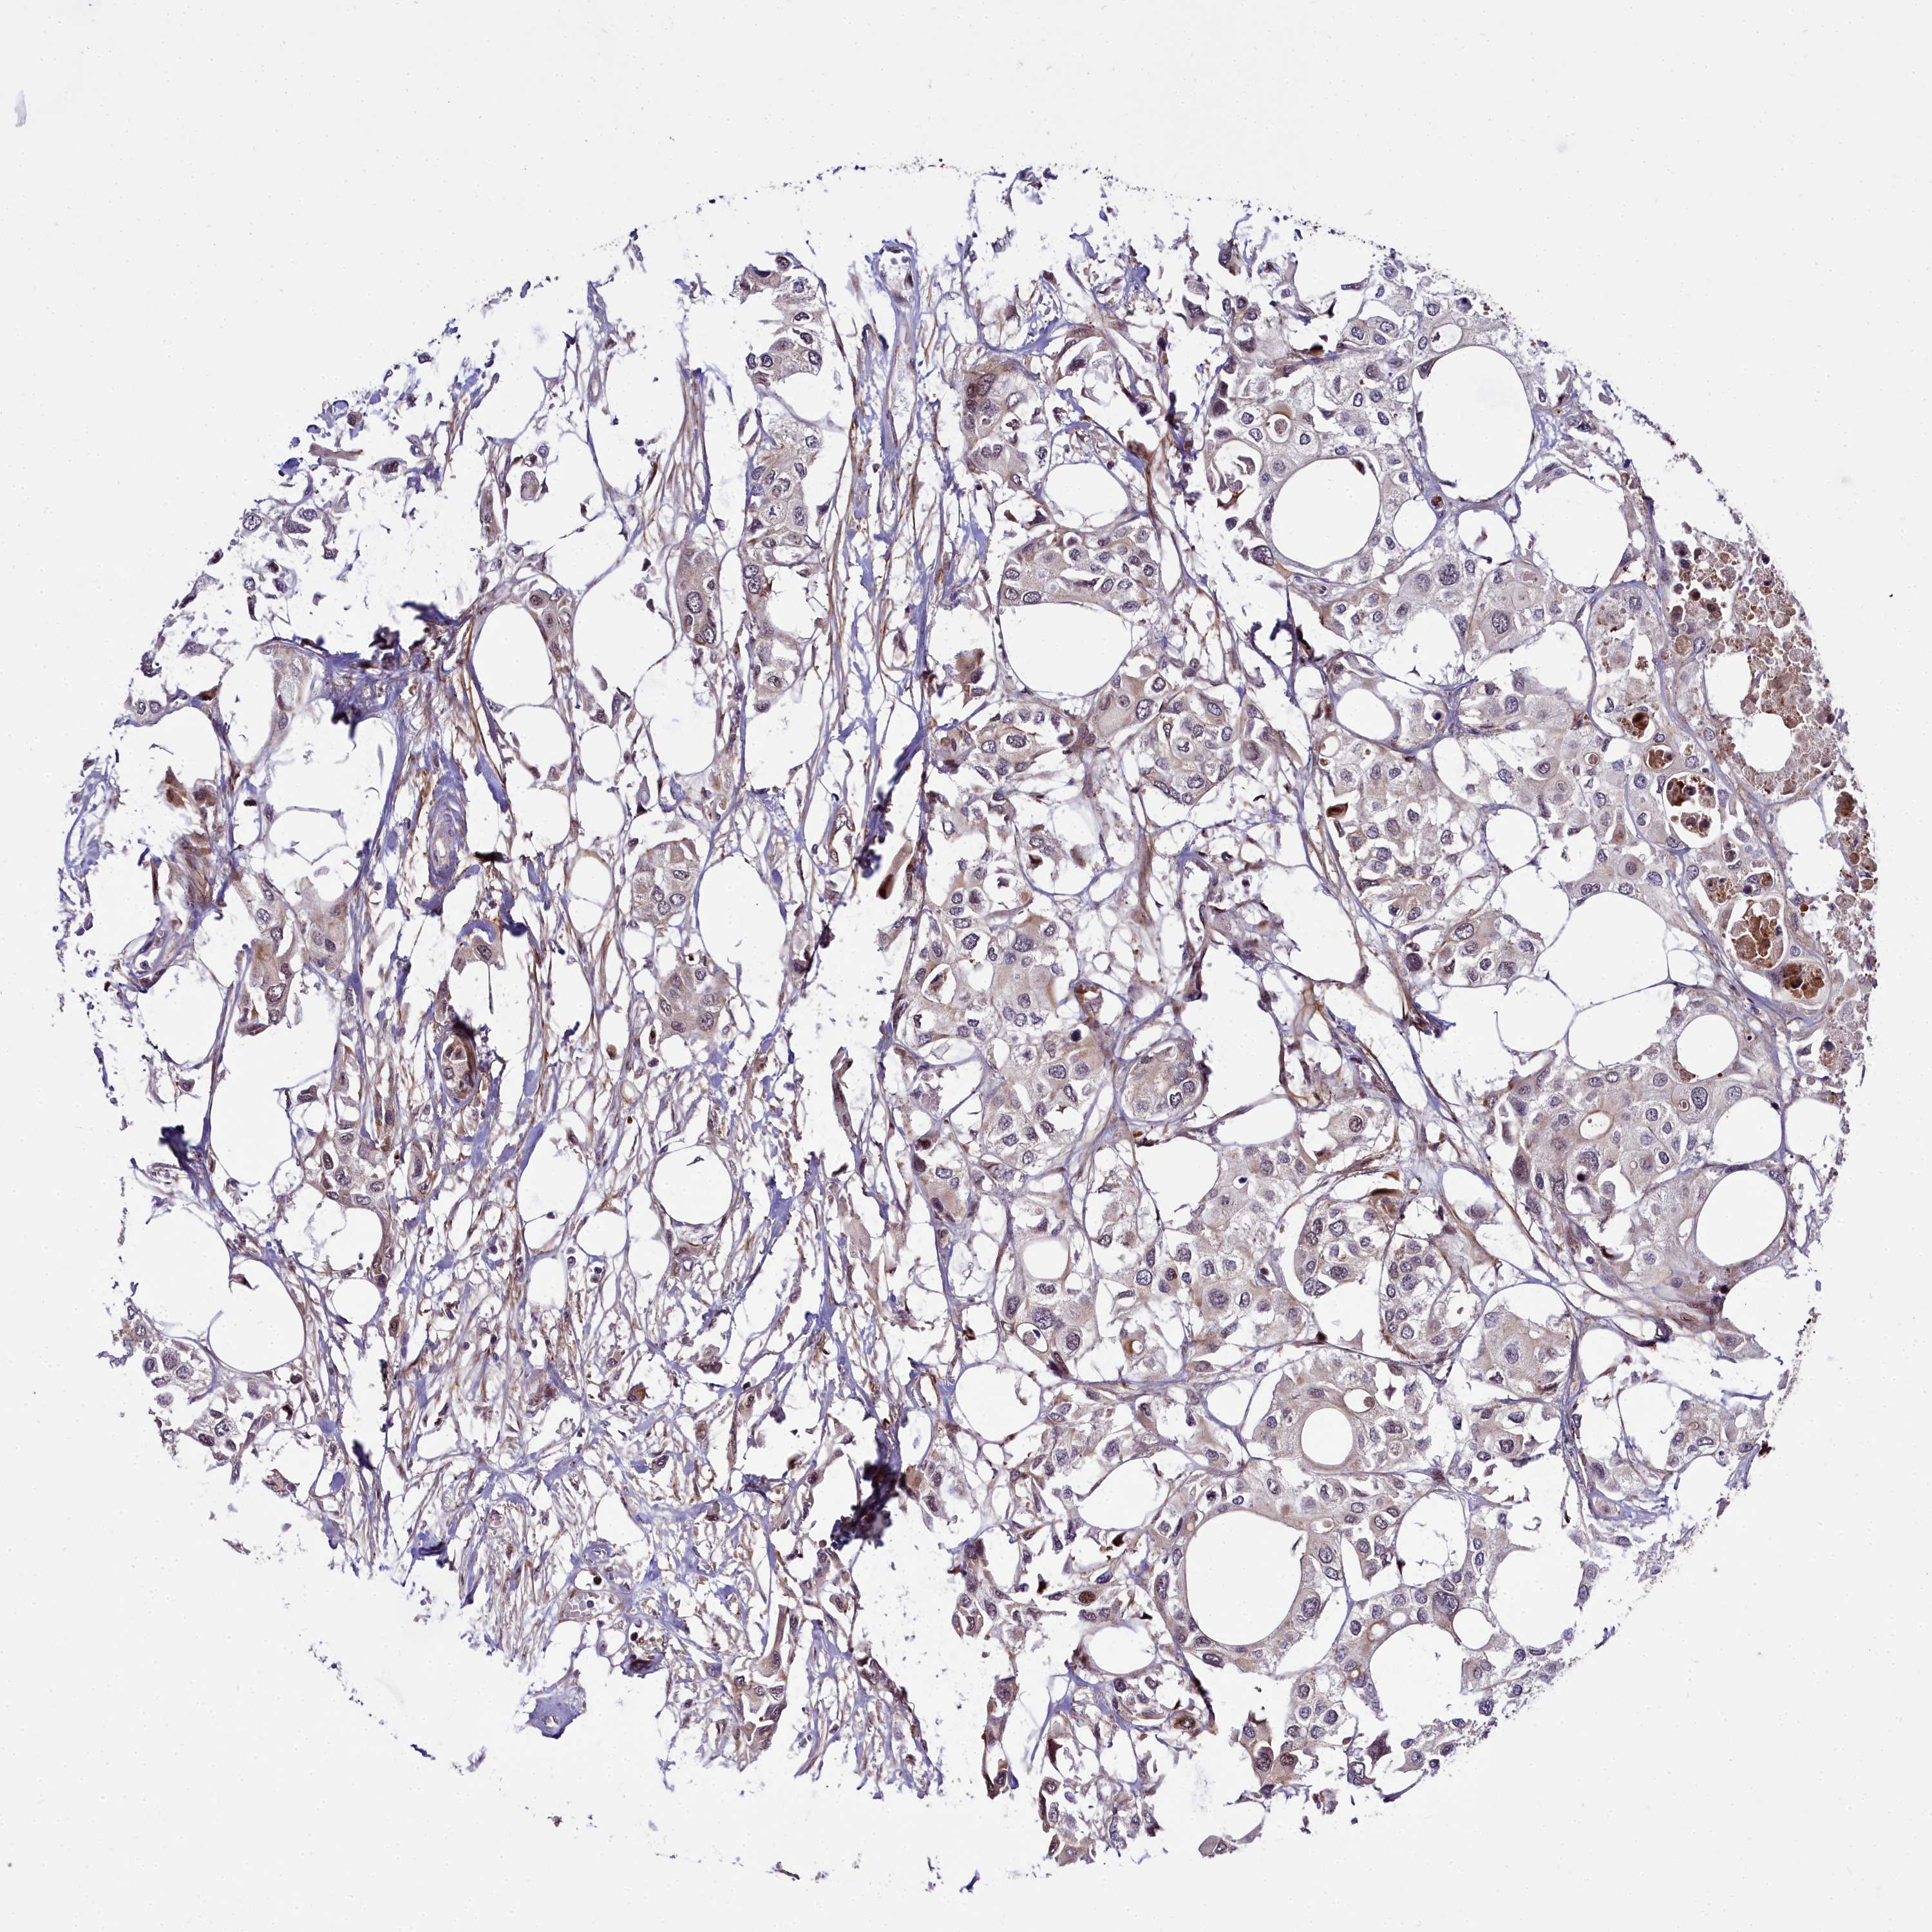

UROTHELIAL CANCER - Protein expressioni

A mouse-over function shows sample information and annotation data. Click on an image to view it in a full screen mode. Samples can be filtered based on level of antibody staining by selecting one or several of the following categories: high, medium, low and not detected. The assay and annotation is described here.

Note that samples used for immunohistochemistry by the Human Protein Atlas do not correspond to samples in the TCGA dataset.

Antibody stainingi

Antibody staining in the annotated cell types in the current human tissue is reported as not detected, low, medium, or high, based on conventional immunohistochemistry profiling in selected tissues. This score is based on the combination of the staining intensity and fraction of stained cells.

Each image is clickable and will lead to virtual microscopy that enables deeper exploration of all samples and also displays staining intensity scores, fraction scores and subcellular localization as well as patient and tissue information for each sample.

Antibody HPA043752

Antibody HPA050345

Staining

High

Medium

Low

Not detected

Intensity

Strong

Moderate

Weak

Negative

Quantity

>75%

75%-25%

<25%

None

Location

Nuclear

Cytoplasmic/membranous

Cytoplasmic/membranous,nuclear

Urothelial carcinoma, High grade

Urothelial carcinoma, Low grade